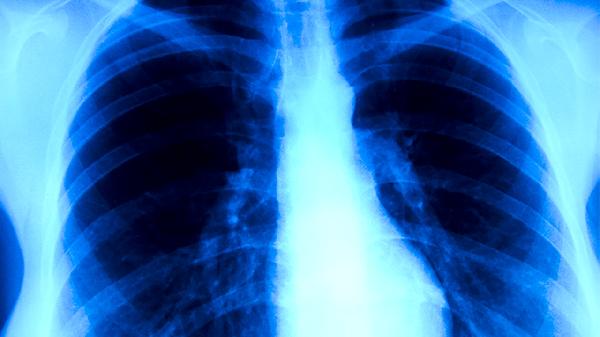

细菌性支气管肺炎主要由肺炎链球菌、流感嗜血杆菌、金黄色葡萄球菌、卡他莫拉菌和肺炎克雷伯菌等病原体感染引起。发病与免疫力下降、呼吸道防御机制受损、慢性基础疾病、环境刺激及病原体毒力增强等因素相关。